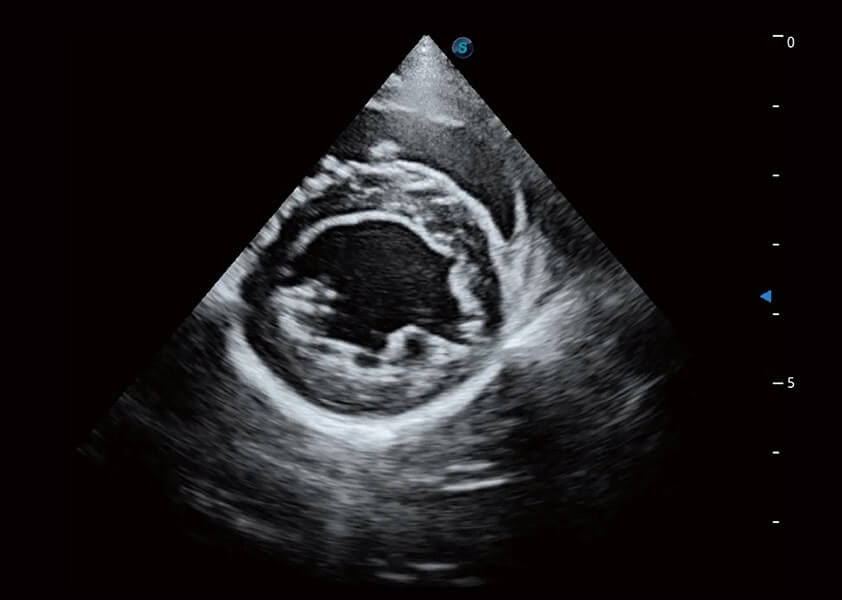

ProPet 60 作为一款高端台式动物超声设备,为动物医生的日常诊断提供了一系列贴合动物临床需求、解决临床实际问题的高级成像功能。凭借全系列高清探头,满足医生对腹部、心脏、生殖、浅表、肌骨等成像的所有需求,切实帮助您提升检查效率,提高诊断信心。

兽用彩色多普勒超声诊断系统

动物是人类最亲密的朋友和最值得信赖的伙伴。竞技宝(JJB)官方网站也一直致力于探索动物专用的超声影像解决方案。 全新推出的ProPet系列,是竞技宝(JJB)官方网站在动物超声影像智能化、专业化、精准化的一次跨越式革新。动物不能用言语来表述自己的不适,通过超声影像,ProPet系列搭建了动物医生与不同物种沟通的“桥梁”,为动物医生注入了“治愈之力”。